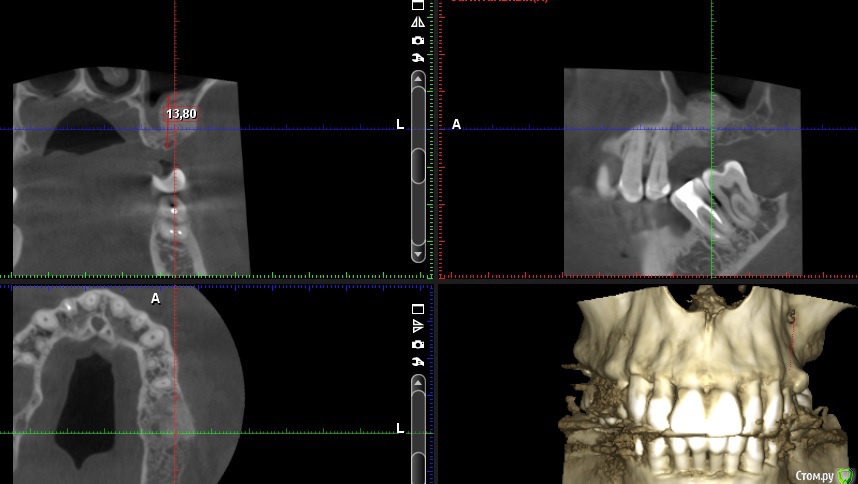

Andre_ Опубликовано 16 июня, 2015 Автор Поделиться Опубликовано 16 июня, 2015 Кхм, в тему "водить трамвай" или "как не надо". Шурупу около 5 мес, заживал как в книжке, чего там с ним - не пойму. Ссылка на комментарий

Имплантатор Опубликовано 29 июня, 2015 Поделиться Опубликовано 29 июня, 2015 Хм... Не вижу смысла в синусе вообще. 6 мм высоты достаточно. Можно просто имплантатом закортикалиться на 1 мм. С таким-то расстоянием до окклюзионной... 1 1 Ссылка на комментарий